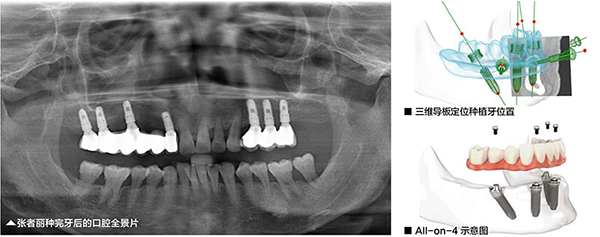

另一个和张者丽一样想让自己的晚年生活过得舒心点的是70岁的刘建华,他的缺牙情况比张者丽更加严重,上下颌没有一颗牙。由于老刘特别怕痛,需要尽更大的可能为老刘提供和快速的全口种植方案。苏州美奥口腔王汉禹院长为刘建华设计的方案是计算机三维专业导板辅助下的All-on-4即刻负重种植牙,当天种牙,当天戴整口牙,当天可以吃饭。

如何在All-on-4的基础上再进一步提升半口种植的性呢?美奥口腔All-on-4即刻负重在术前为患者定制计算机三维专业种植导板,让种植专业度提升,种牙手术时间缩短,创口更小,创口暴露时间更短,术后恢复更快。

三维专业种植导板在种植手术前,利用三维重建软件,详细测量患者牙床的骨质密度、牙槽骨本身的高度、宽度等条件,测量出患者哪一块牙床骨条件好,适合植入人工牙根,哪一处骨量偏低,需要避开或进行植骨,并通过这些专业数据在计算机辅助下制作出手术中使用的导板。也就是说在真实手术前,医生就在计算机生成的三维影像上进行了一次种植手术预演,预先标注专业的种植位置,最终制作成一个种植导板。

患者在手术时,将导板佩戴在口腔内,医生可以根据导板上的标注位置确定种植位置,而不是通过传统的人眼目测,大大提高了种植的专业性和降低手术风险,手术时间大幅度缩短,降低了患者的痛苦,条件允许可实现微小切口、不翻瓣、无缝合的手术治疗。